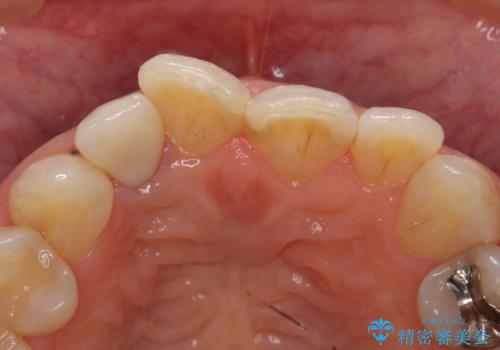

- 右上2番目の歯の変色が気になるといらっしゃった方の症例です。

再根管治療終了後、オールセラミッククラウンによる補綴を行いました。